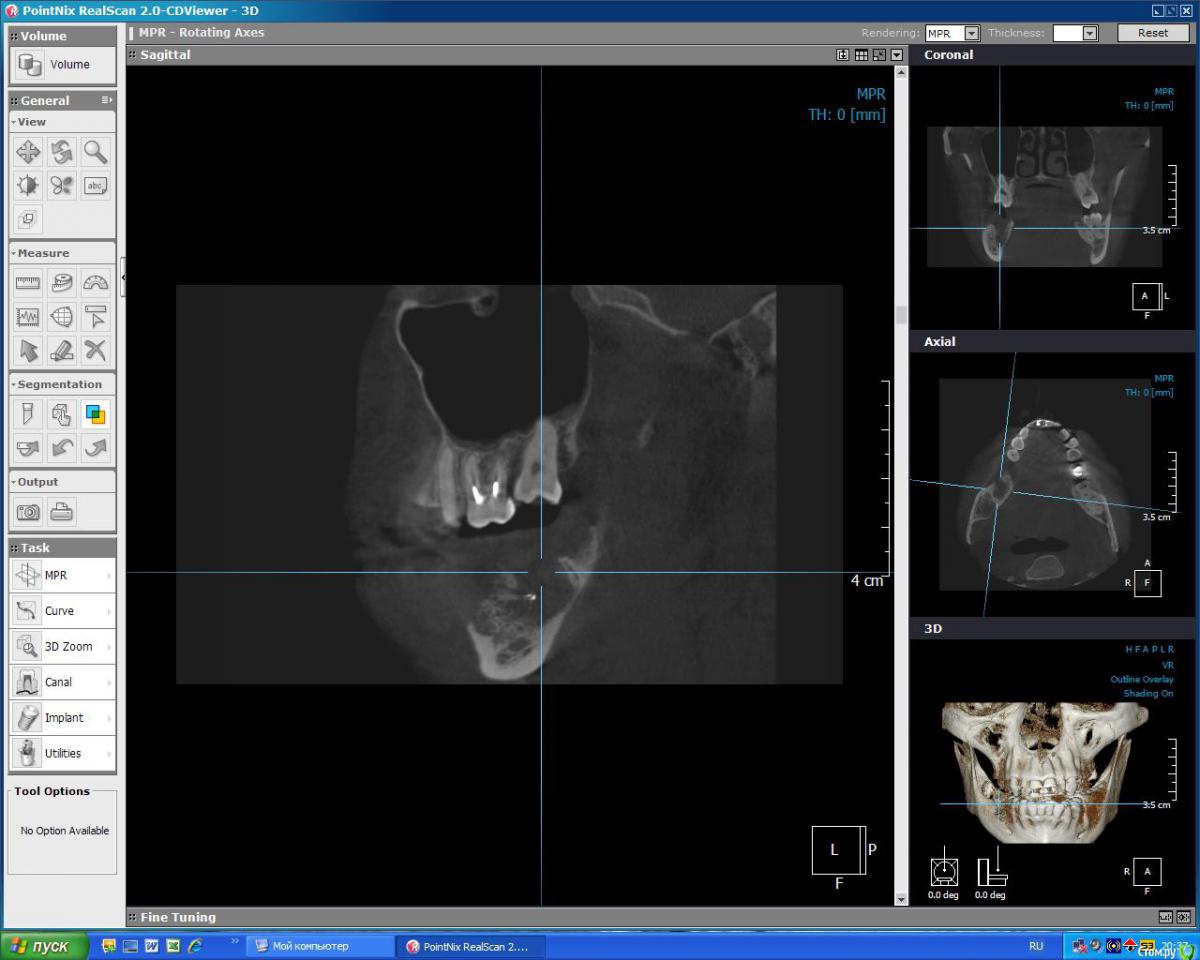

kuznetsovaev Опубликовано 19 октября, 2015 Поделиться Опубликовано 19 октября, 2015 (изменено) Добрый вечер, уважаемые врачи, подскажите мне пожалуйста какой вариант имплантации более правильный. Буду очень надеяться на вашу помощь. Так же буду рада если будут еще какие-то может более верные варианты. Заранее благодарю. Были кисты на верхней и нижней челюсти, в связи с чем удалили зубы.КТ от 10.10.2015г. Мне 33, пол женский.Верх лево: 7зуб и киста над ним удалены 18.09.2015, соседний 6-ой удален 3года назад.Низ право: 6-ой зуб удален 20.04.2015, киста и 7-8 зубы удалены 13.08.2015г. Пока хожу по клиникам ищу "своего" врача и слышу разные мнения. Вариант 1.1. Нижние 6 и 7 импланты ставить без костной пластики через пару месяцев (в декабре), кость сама нарастет. Сделать прицельный снимок перед имплантацией и все, т.к. очертания кости уже видны, кость просто станет более плотной, а границы уже не изменятся.2. Верхние 6 и 7 ставить через полгода после синуслифтинга. Вариант 2.1. Нижний 6 без костн.пластики, а в 7 лунку пересадить свой костный материал закрепив минигвоздиками (если правильно запомнила). Спустя три месяца ставить импланты сразу в 6 и 7.2. Верх синуслифтинг над 6 и 7кой, через полгода ставить и 6 и 7 имплантат. В этом варианте прозвучала еще мембрана и 4 болтика, я не поняла куда ее крепить будут. Вариант 3.1. Низ 6 готова к имплантации, а в 7ку засыпать микс кости моей и инородной. Спустя два-три месяца ставить импланты сразу в 6 и 7.2. А на верхней челюсти над 6-ой подъем пазухи, а над 7-кой не надо поднимать, а нужно засыпать в ее лунку смесь моей и инородной кости, закрыть мембраной. Ну и через полгода имплантация. Вариант 4.1. Внизу без костной пластики.2. Верх через закрытый синус досыпят кости с одновременной имплантацией. Изменено 19 октября, 2015 пользователем kuznetsovaev Ссылка на комментарий

faity Опубликовано 21 октября, 2015 Поделиться Опубликовано 21 октября, 2015 удаление 2.8, 3.8брекетычерез год после начала лечения синуслифтинг с имплантацией 2 сегмент(слева сверху)через 4 месяца после синуса имплантация 4 сегмент(снизу справа)снимаем брекетыставим коронки на импланты и на 1.6, 1.5, 2.5, 3.6 после ревизии каналов 1 Ссылка на комментарий